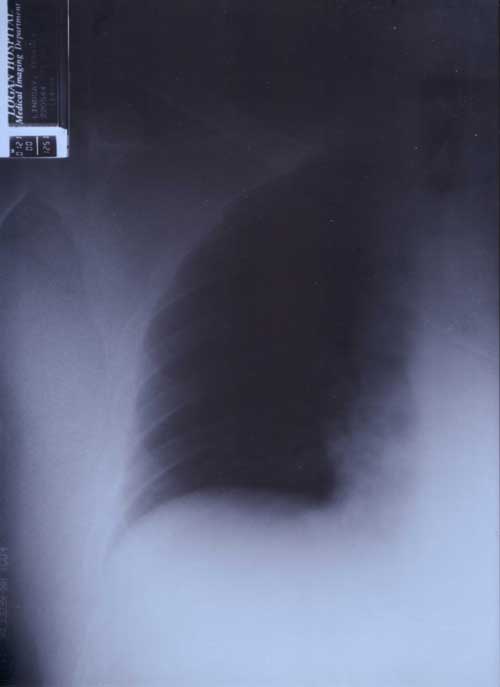

21st January 2000